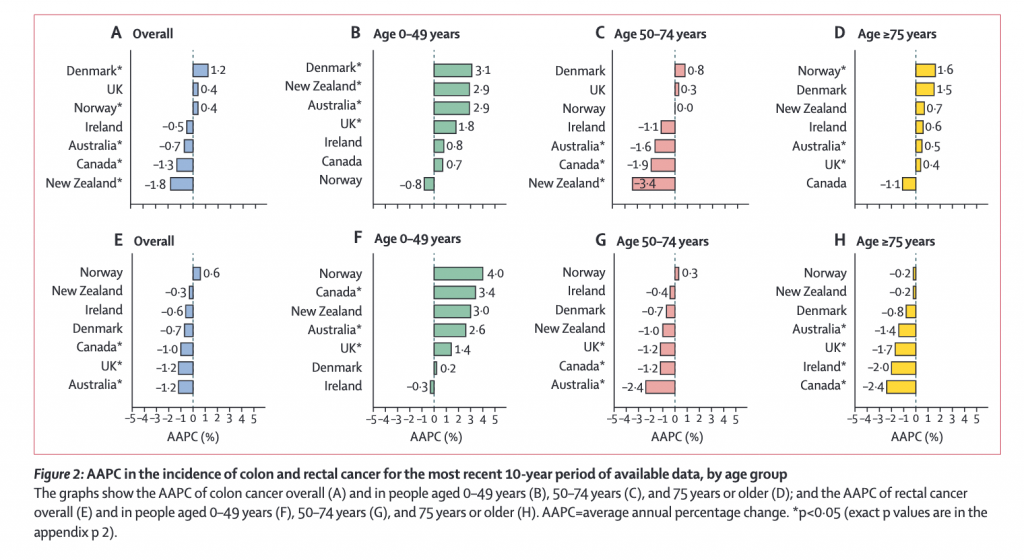

We recently reported an animal study showing that high-fructose corn syrup may be a contributing factor to the rising rates of colon and rectal cancer among young adults. A new observational study from The Lancet Gastroenterology & Hepatology journal looked at long-term data for colon and rectal cancer incidence in 21 population-based registries across Australia (1983-2012), Canada (1995-2014), Denmark (1978-2012), Ireland (1995-2013), New Zealand (1995-2014), Norway (1953-2014), and the UK (1995-2014). It shows that the incidence of colon and rectal cancer in adults younger than 50 years has increased substantially over the latest available 10-year period in certain high-income countries.

In The Lancet data, during the most recent 10-year period up until 2014, the incidence of colon cancer in people aged

Across the same time period, significant decreases in incidence of colon cancer per annum were observed in those aged over 50 in Australia (by 1.6%), Canada (1.9%), and New Zealand (3.4%) and of rectal cancer in Australia (2.4%), Canada (1.2%), and the UK (1.2%).

Trends in the incidence of colon and rectal cancer by age group showed diverging pattern (See Figure 1 and Figure 2 below):

- In people aged 0–49 years, the incidence of colon cancer increased significantly in Denmark (by 3·1%), New Zealand (2·9%), Australia (2·6%), and the UK (1·8%) over the most recent 10-year period (figure 2B), and these increases were more pronounced in women and girls than in men and boys

- In people aged 0–49 years, an increase in incidence was noted particularly for tumors occurring in the distal (left-side) colon (appendix pp 5, 11). In people aged 0–49 years, the incidence of rectal cancer increased significantly in Canada (by 3·4%), Australia (2·6%), and the UK (1·4%; figure 2F).

- Analyses by age subgroup showed that, among people aged 20–29 years, there were significant and large increases in the incidence of colon cancer in Denmark and Australia, and a significant decrease in incidence this age group in Canada (figure 3; appendix p 6).

- There was also a significant increase in the incidence of rectal cancer among people aged 20–29 years in Denmark. The increasing incidence of colon cancer was driven largely by increases in the incidence of distal colon cancer both overall (appendix pp 5–6, 11) and in people aged 20–29 years (appendix p 7).

The authors of the study suggest that the decrease in incidence of colorectal cancer in people over 50 years old in most of the countries studied could be attributed to the introduction of routine screening programmes for premalignant polyps. In Australia, Canada, and the UK, where age-based screening began in 2006, overall decreases in incidence were more pronounced. In those countries where screening programmes began later, such as in Ireland (2012), Denmark (2014), Norway (2012, pilot programme only), and New Zealand (2017), overall rates have remained roughly stable.